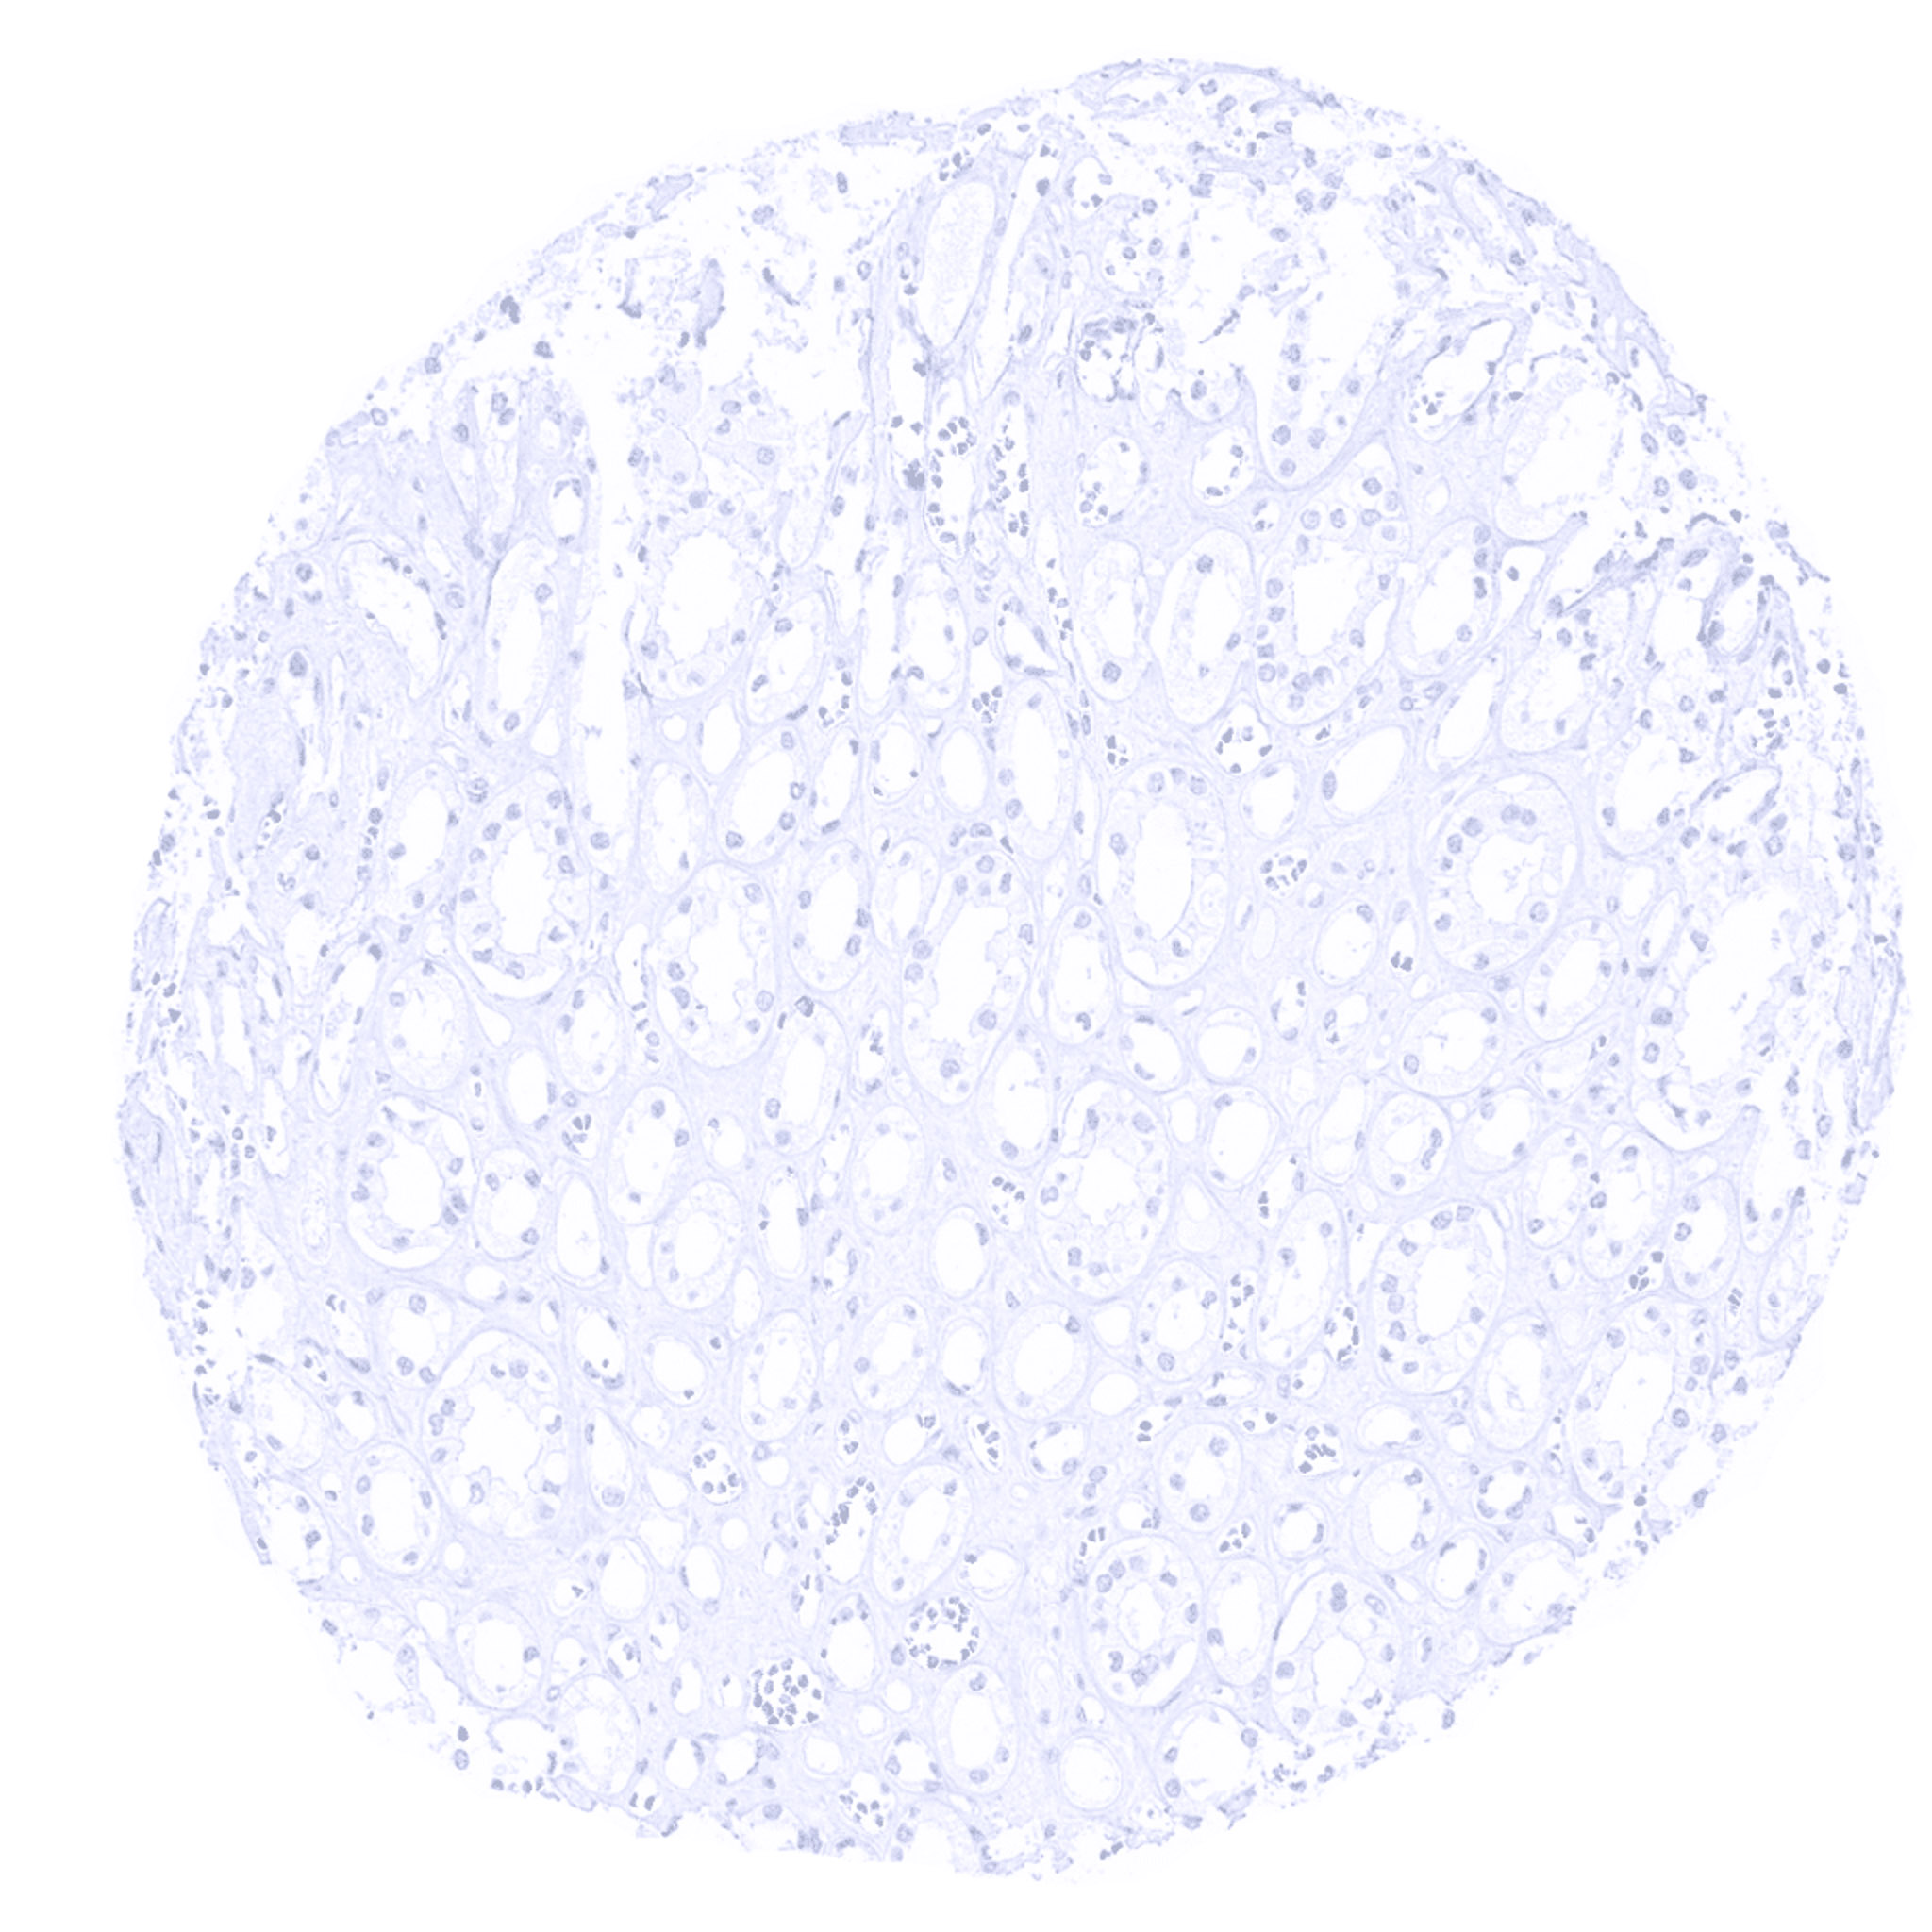

Thyroid gland